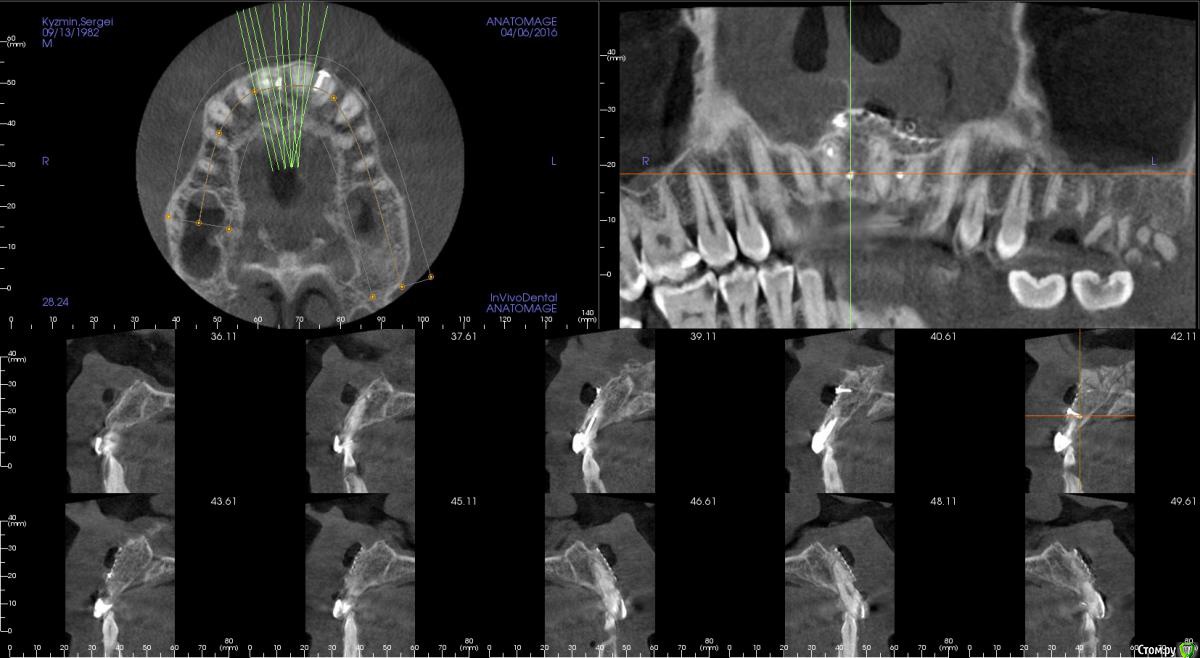

kamranchick Опубликовано 17 апреля, 2016 Поделиться Опубликовано 17 апреля, 2016 Пришел пациентДок привет, что то зуб шатается, можно ли его оставить, вот такие дела)как бы вы поступили бы? Ссылка на комментарий

dantist_movani Опубликовано 27 апреля, 2016 Поделиться Опубликовано 27 апреля, 2016 Пришел пациентДок привет, что то зуб шатается, можно ли его оставить, вот такие дела)как бы вы поступили бы?1)проверил бы на витальность2)Репозиция и шинирование орто ретейнером с жидкотекучим композитомпохожая ситуация была год назад, правда отлом кортикалки не столь значительный был. Ретейнер снял через 6 мес, все Ок, зуб не почернел♿, эод -8 в дуге, пац очень доволен Ссылка на комментарий